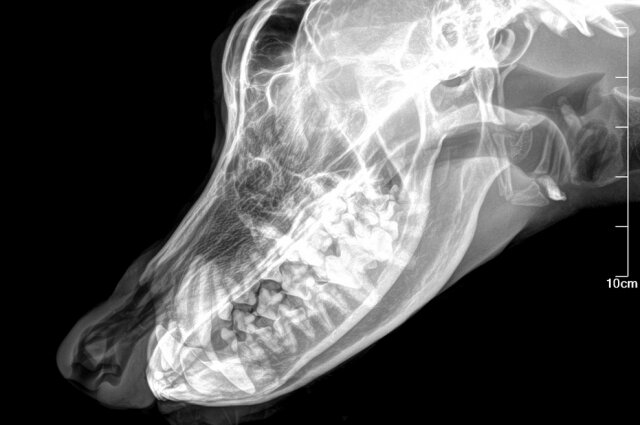

«Пес очень сильно исхудал. Ребра и кости черепа торчат на худом теле через шерсть. Увидев его, просто невозможно сдержать слез - пушистый скелет прыгает, виляет хвостом и скулит сквозь плотно сомкнутые челюсти. Повезли его к ветеринарам. Врачи сделали рентген в нескольких проекциях, но не нашли проблемы! Собаке вкололи седацию, но даже под ней врач с ассистентом вдвоем не смогли разомкнуть плотно сжатые челюсти собаки. Пробыв на приеме почти 3 часа нам пришлось уехать ни с чем и вернуть собаку в ее будку», - рассказали волонтеры.

Вторым заходом Ричарда повезли в ветклинику «Виту». Его принял врач Евгений Александрович Козлов. Он подтвердил диагноз - эозинофильный миозит. И, к сожалению, прогноз дал плохой - на фоне длительного миозита начался некроз тканей, скорее всего мышцы работать не будут никогда, челюсти не разожмутся и собака останется жить в таком состоянии.

Фото: Из архива/ Инициативная группа по защите животных г. Тверь